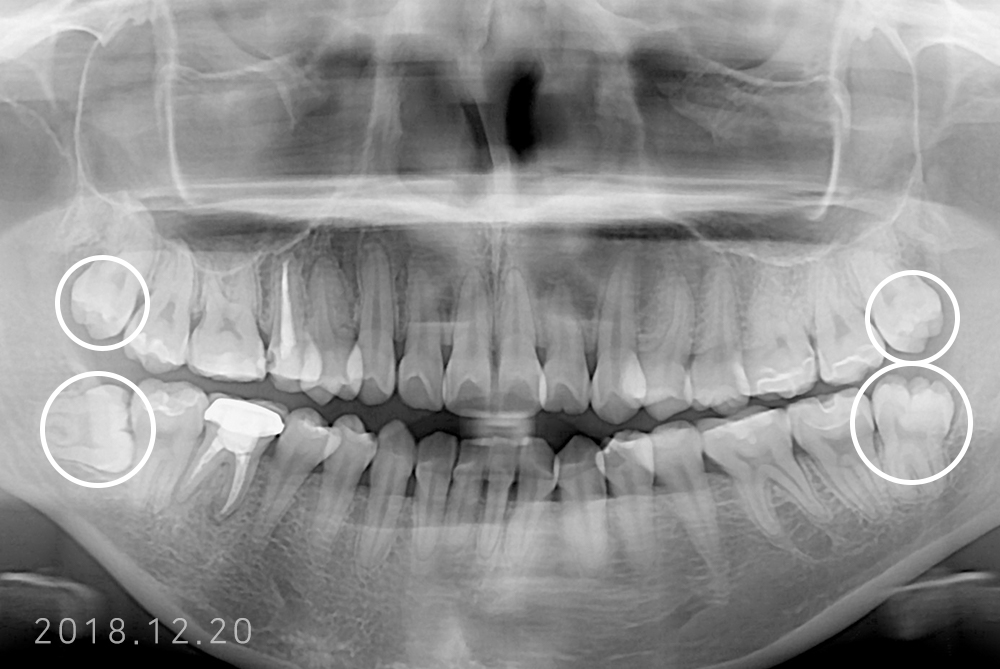

[사랑니] 매복 사랑니 발치

치료전 : 2018-12-20

권은성 후.jpg

치료후 : 2021-12-22

세종치과는 구강악안면외과학 박사이신 원장님이 발치하는 치과입니다.